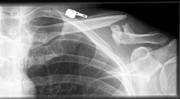

Schlüsselbeinbruch - das Ende der Reise